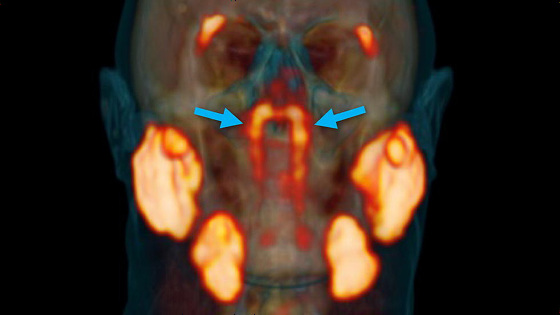

上圖可以看出,新的器官正位於上圖中箭頭標註的發光的地方,其他發光的地方就是我們以前認為的唾液腺所在的位置。

研究小組起初是通過放射性示蹤劑來研究前列腺癌的,這種放射性示蹤劑在進入人體以後會與前列腺癌細胞中的蛋白質PSMA (前列腺特異性膜抗原)結合,這其實就是癌細胞被標記的過程。

然後通過掃瞄追蹤放射性示蹤劑我們就能知道癌細胞的位置,這種利用示蹤劑成像診斷法被稱為“PSMA PET-CT”。

不過PSMA這種蛋白質不僅存在於前列腺癌細胞中,在人體的唾液腺阻止中也存在,因此在掃瞄成像的過程中就標記出了人體中所有唾液腺的位置。

也正是通過以上的方法, 研究小組意外的發現了新的唾液腺,並且把這種新發現的器官命名為“Tubarial Glands (管狀腺)”